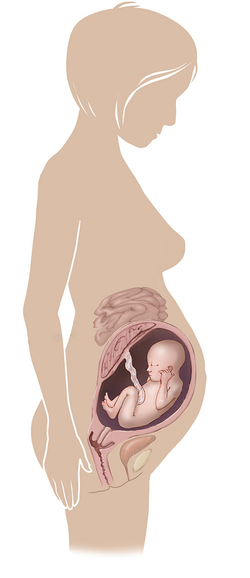

مراحل تطور الجنين أثناء الحمل

تطور الجنين خلال فترة الحمل على ثلاثة مراحل: أول 14 أسبوع من الحمل ، ثم تطوره بداية من الأسبوع 14 وحتى 28 أسبوعا ، ثم الثلث الأخير من 28 إلى 40 أسبوع من الحمل ... المزيد

مراحل تطور الحمل أسبوعيا بالصور

مراحل تطور الحمل أسبوعيا لكل من الأم والجنين داخل الرحم مدعومة بالصور التوضيحية ... المزيد